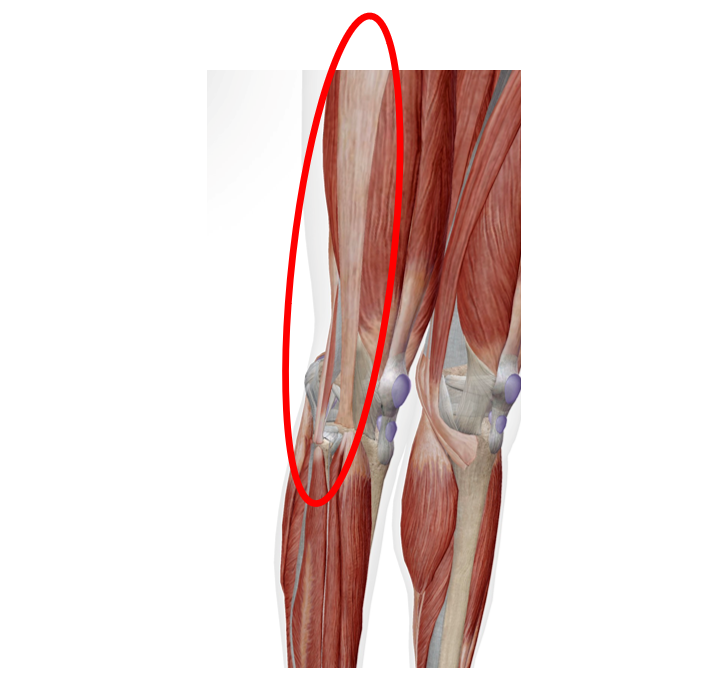

赤い丸のあたりが痛むでしょうか?

今回は「膝の外側の痛み」について解説します!

腸脛靭帯(上の図の位置にあります)炎の症状としては、運動後に膝の外側に痛みが出ます。痛みが出る場所は、膝の外側の出っ張っている部分です。また久しぶりにランニングをしたり、運動をすると痛いことがあります。